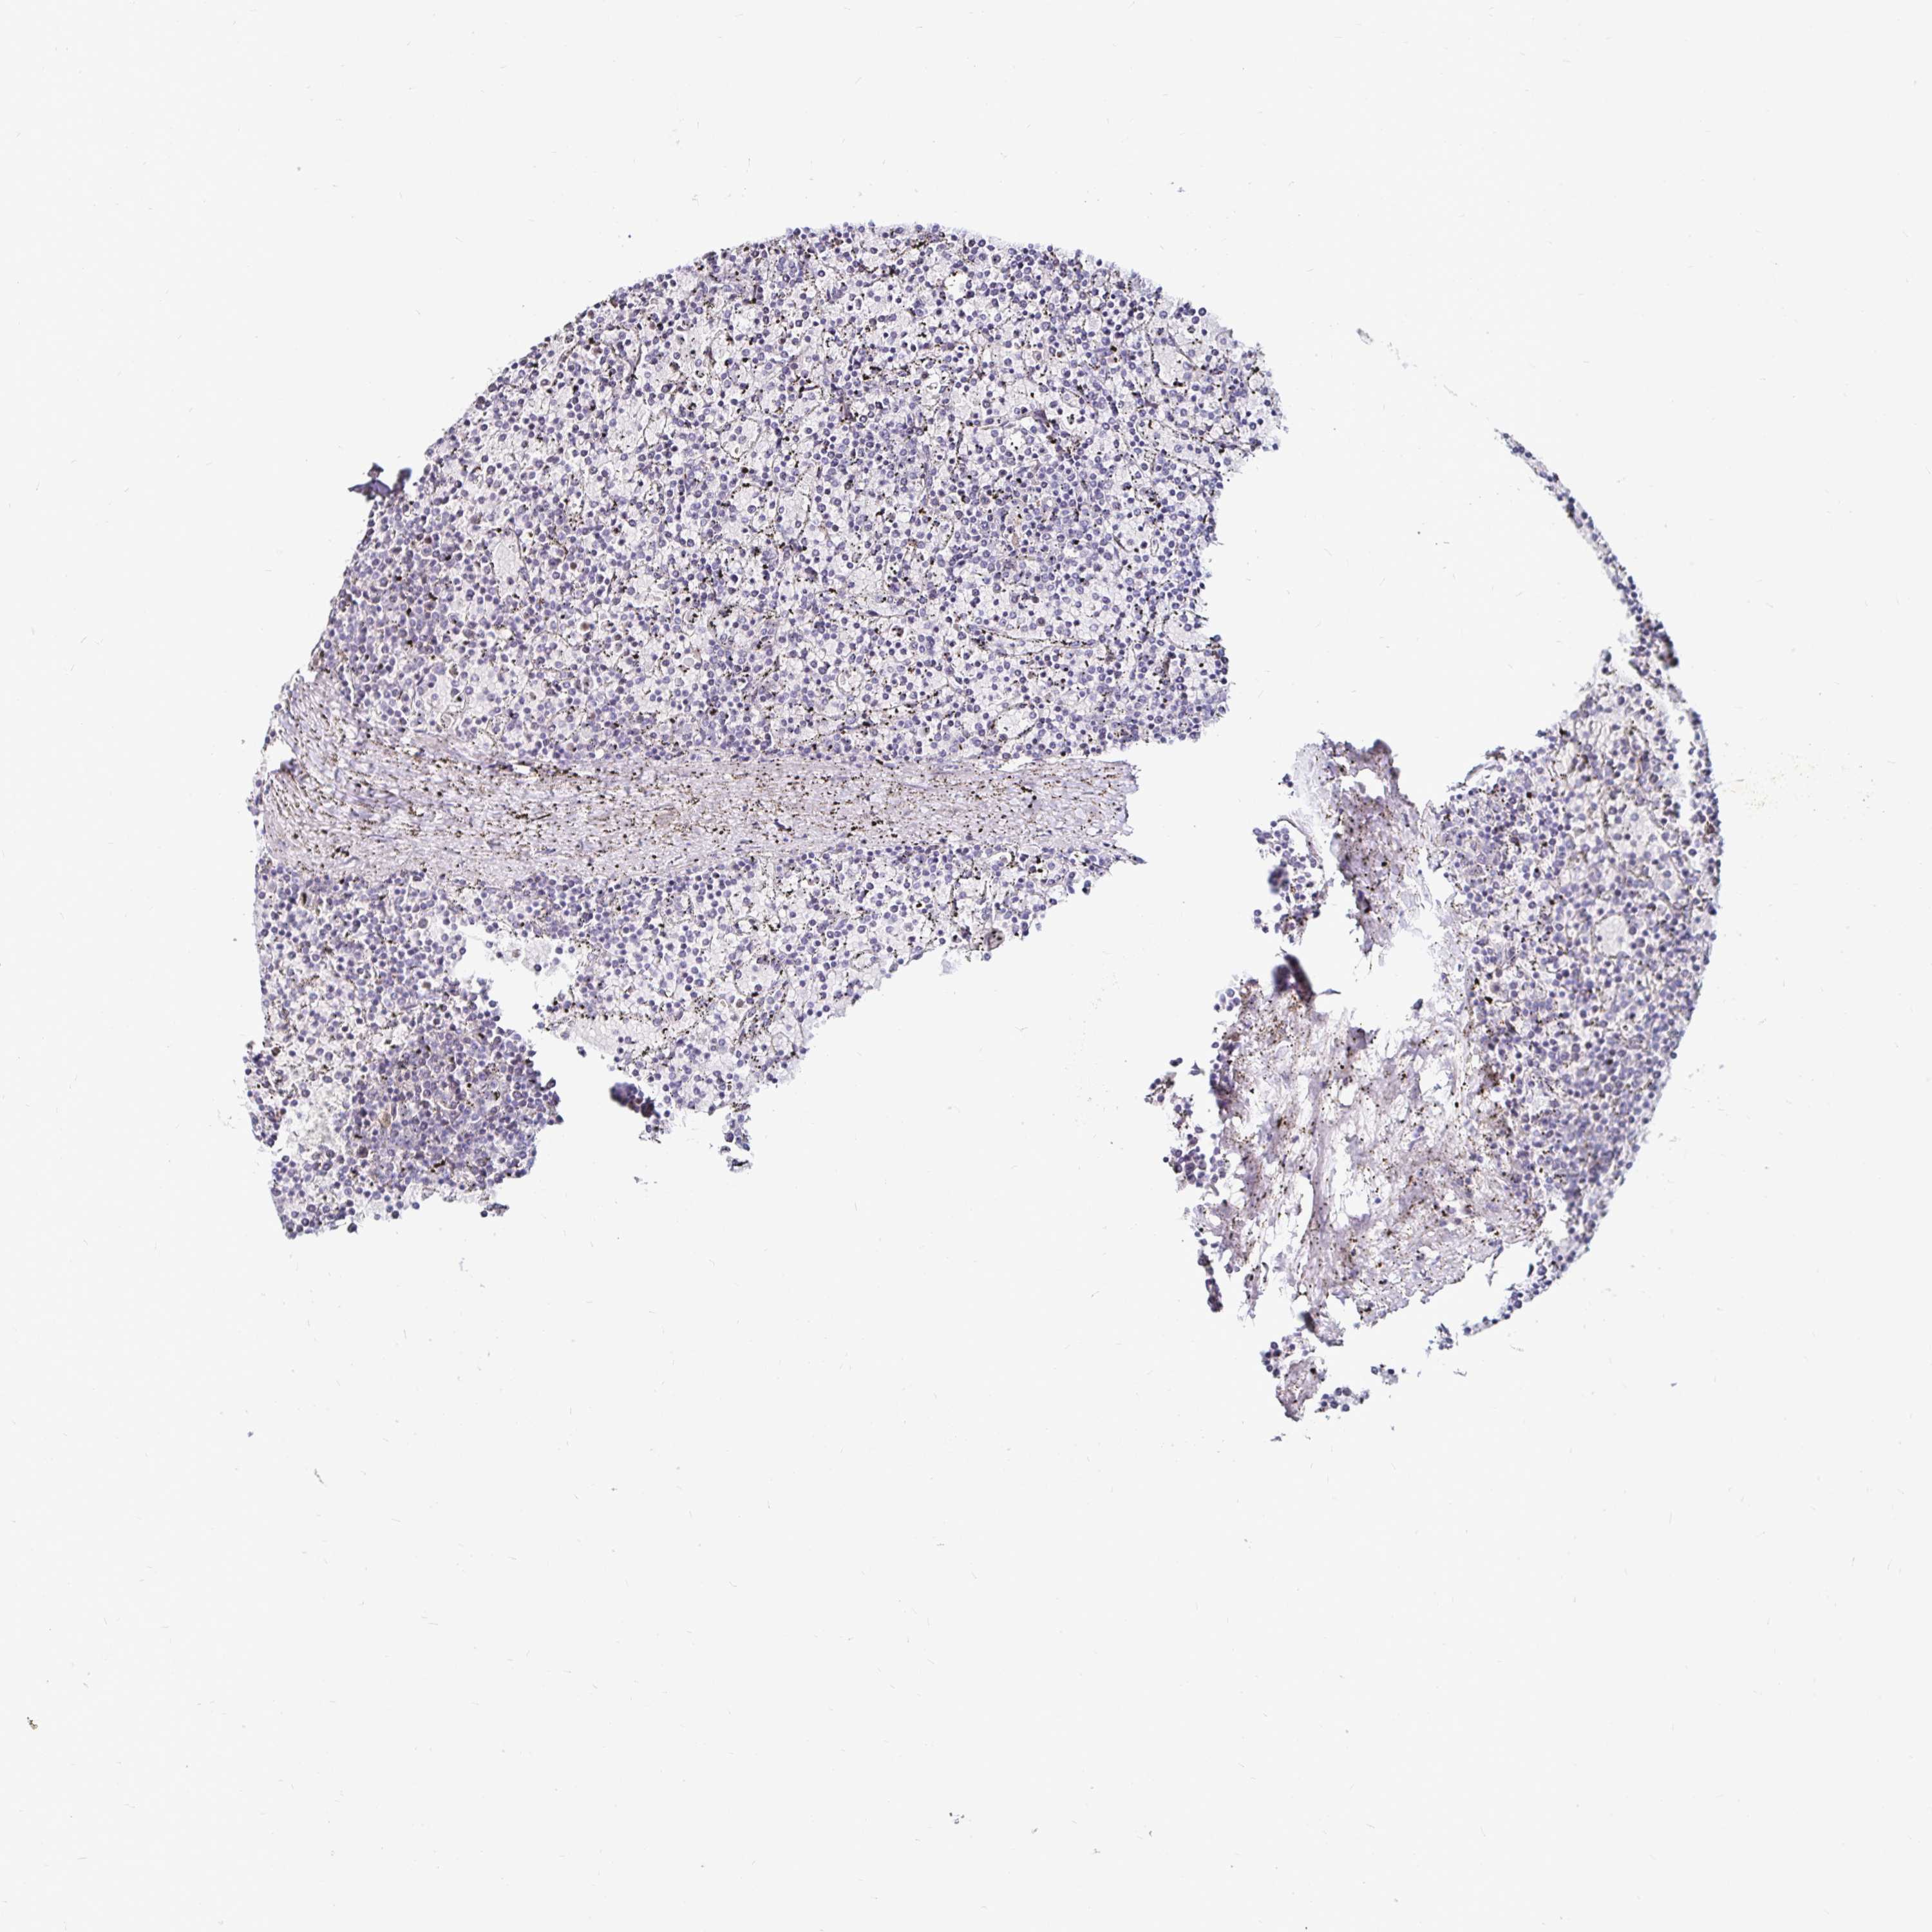

LYMPHOMA - Protein expressioni

A mouse-over function shows sample information and annotation data. Click on an image to view it in a full screen mode. Samples can be filtered based on level of antibody staining by selecting one or several of the following categories: high, medium, low and not detected. The assay and annotation is described here.

Antibody stainingi

Antibody staining in the annotated cell types in the current human tissue is reported as not detected, low, medium, or high, based on conventional immunohistochemistry profiling in selected tissues. This score is based on the combination of the staining intensity and fraction of stained cells.

Each image is clickable and will lead to virtual microscopy that enables deeper exploration of all samples and also displays staining intensity scores, fraction scores and subcellular localization as well as patient and tissue information for each sample.

Antibody HPA048800

Hodgkin's disease, NOS

Malignant lymphoma, non-Hodgkin's type, High grade

Malignant lymphoma, non-Hodgkin's type, Low grade